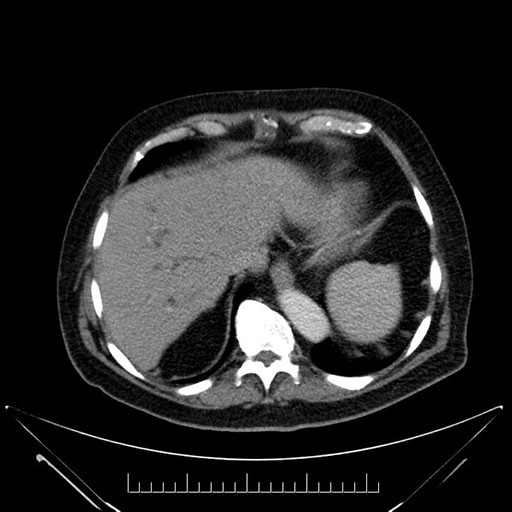

Whipple (pancreaticoduodenectomy) [case 7]

Imaging Analysis

Look through the patient's CT scan to identify any areas of concern for the necessary procedure.

Axial - 3 months prior